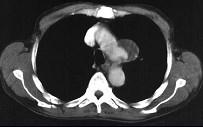

问题 男性,53岁,2年前被踢伤胸部,最近感胸部不适,常规胸片检查,示纵隔内病变,加扫CT平扫及增强,结果如图所示 ( )

选项 A、球形病灶外围见半月形低密度影,其内有斑片状高密度影,考虑为血栓形成 B、结合临床,考虑为主动脉假性动脉瘤(外伤性) C、CT增强扫描示主动脉弓层面左侧缘不规则,造影剂流入球形病灶内 D、结合临床,考虑为主动脉夹层 E、胸片示上纵隔见类圆形高密度影,以侧位片明显

答案 ABCE